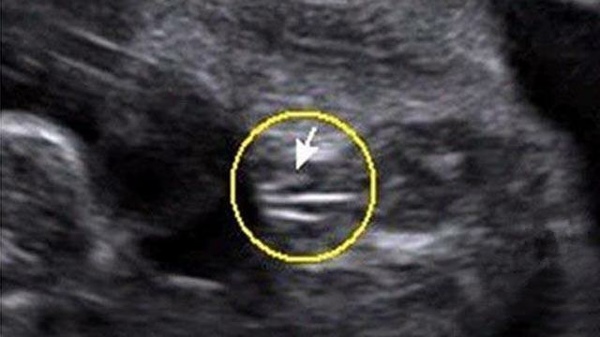

B超上三條線可能是女孩

1、三條線

上圖大致代表女寶的生殖器結構,上面有類似于線條的一杠,這就是女寶胎兒的外生殖器結構了,也就是我們所說的大小陰唇,有的時候b超看到是一條線,大多時候是三條,有這一點,女寶就更好確認了。孕周大了之后,這個時候性別特征不僅很明顯,而且非常清晰好分辨,看男女基本都是十有八九的事情;